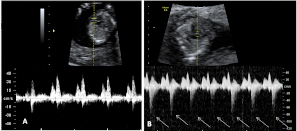

Ecografía Embarazo 2D y 3D Semana 12 - PRUEBAS DIAGNÓSTICAS

Ecografía Embarazo 4D Semana 12 - PRUEBAS DIAGNÓSTICAS